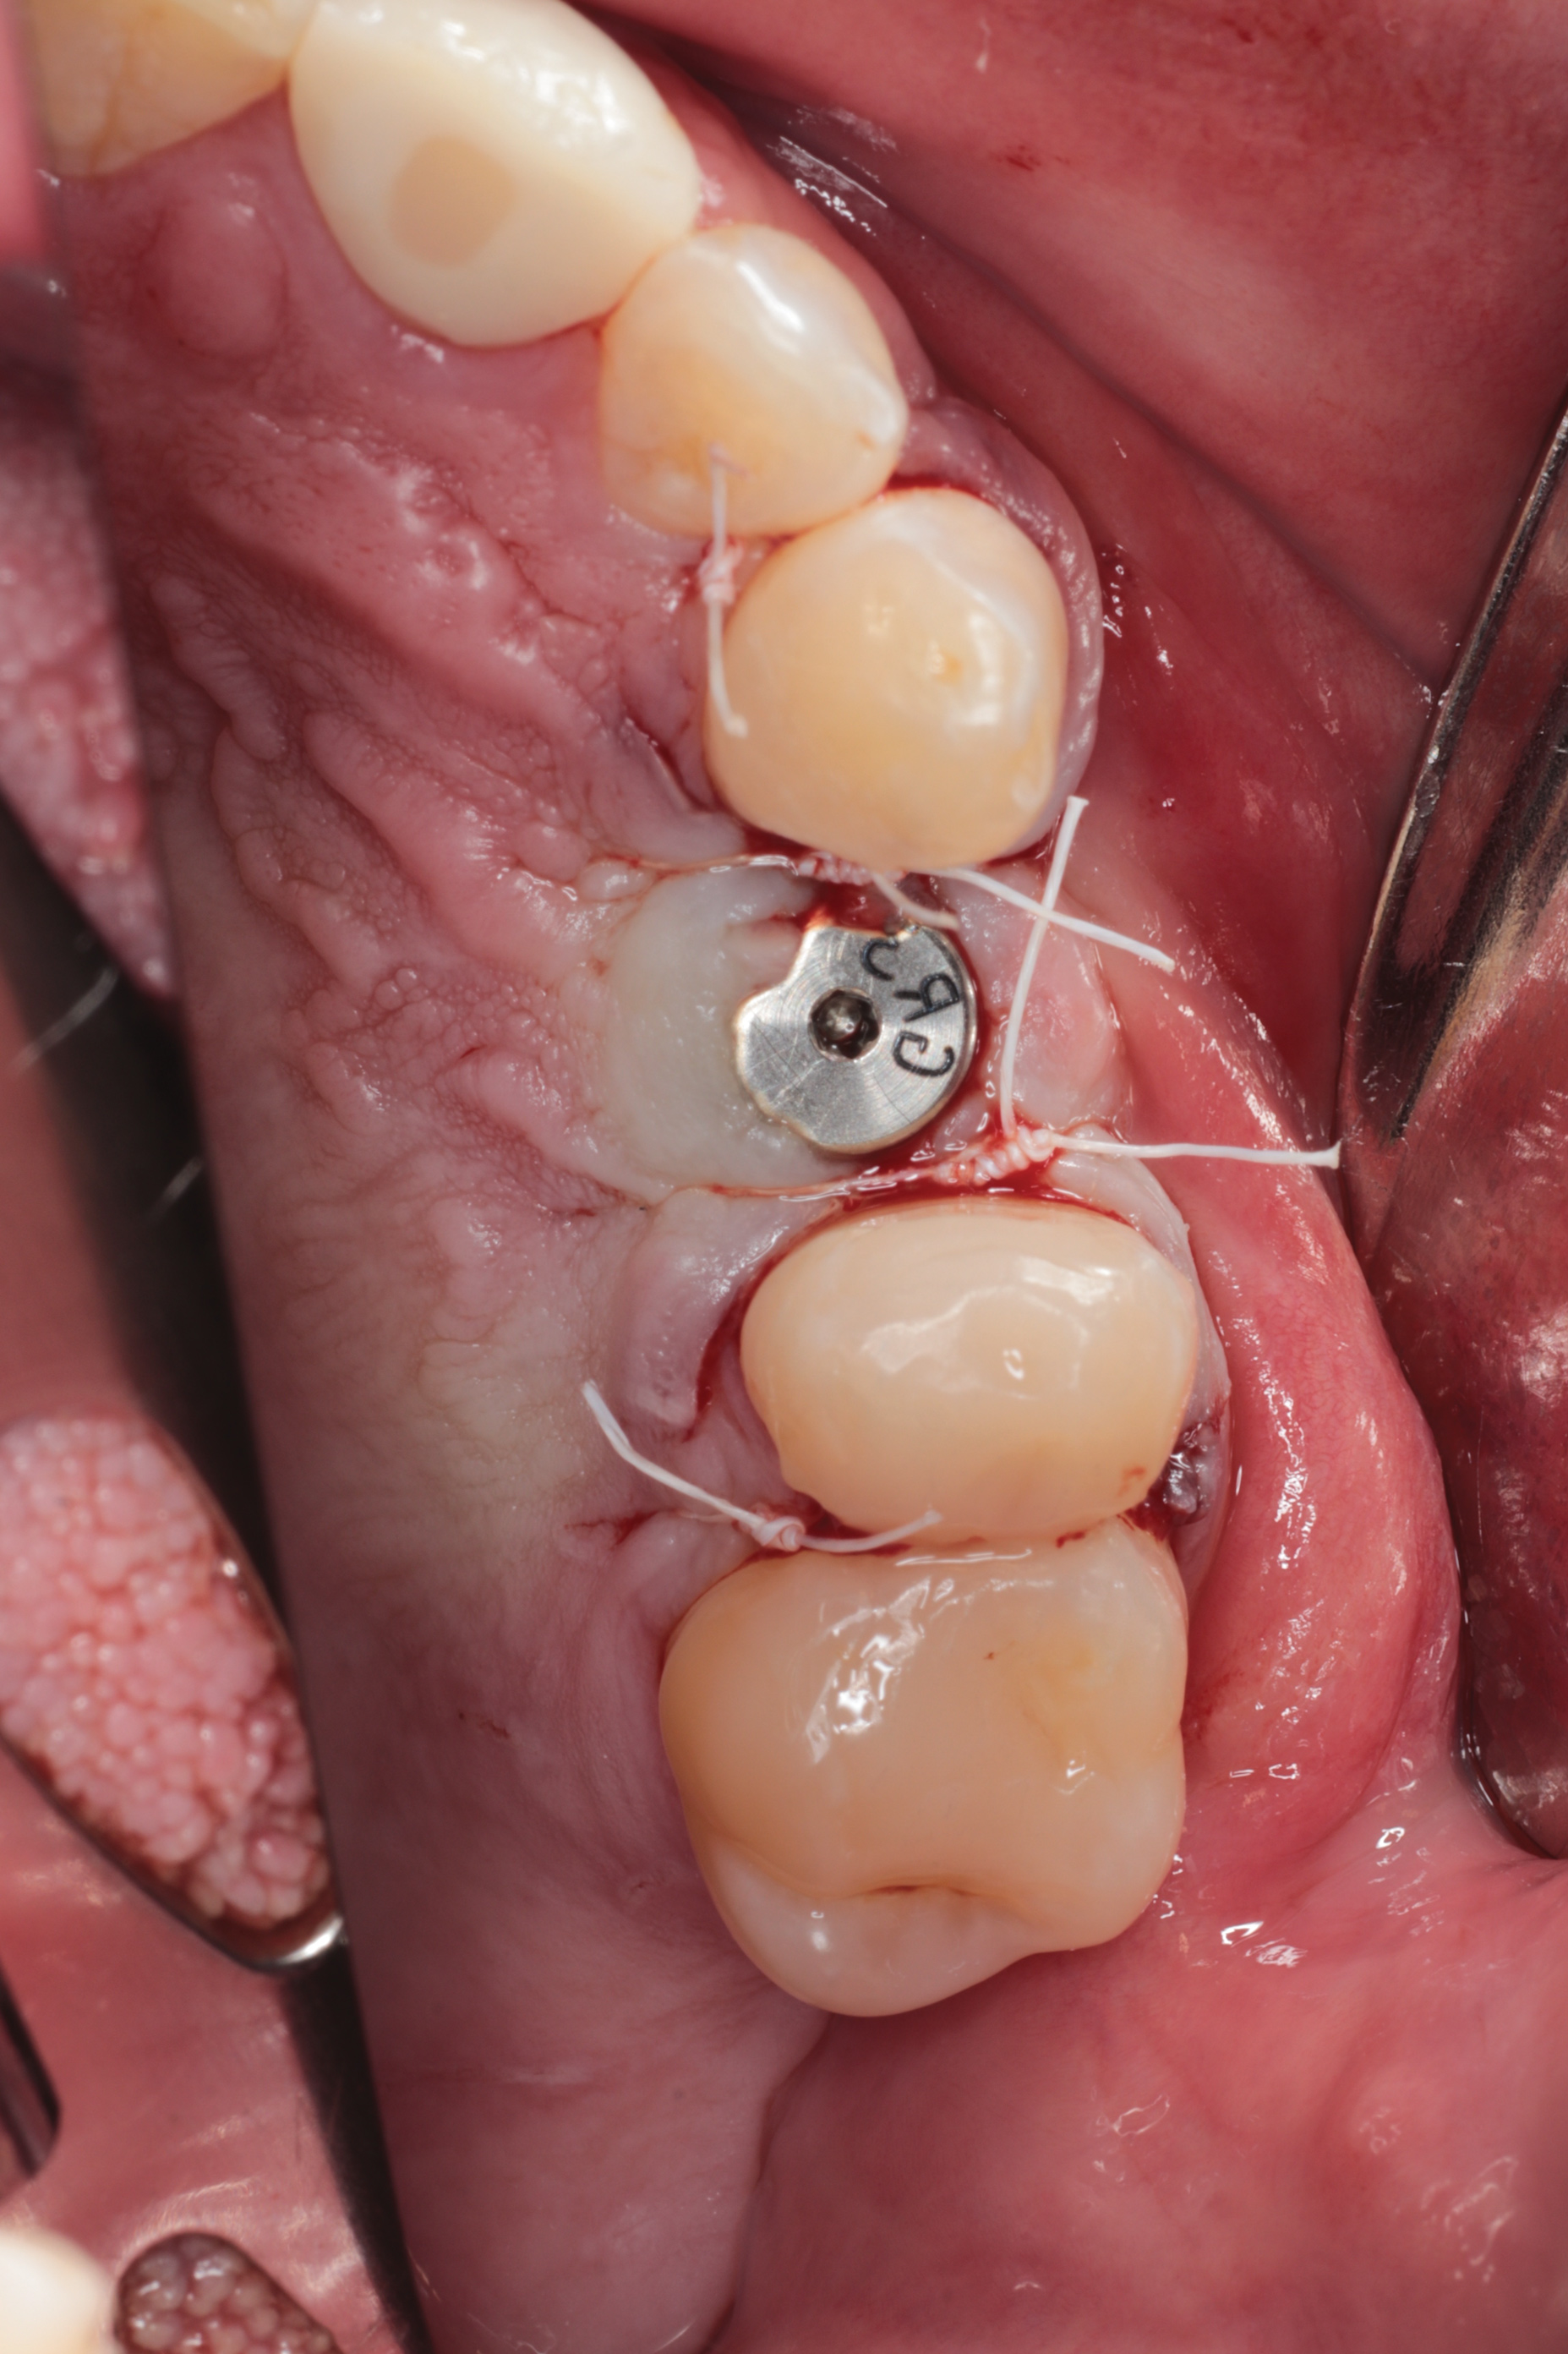

Fig 14. After implant placement, soft-tissue closure was accomplished with 3.0 PTFE suture.

Figure 14

Fig 15. A series of intraoperative x-rays demonstrating sequential use of OD burs along with graft and implant placement. Note graft confinement at the apex of the implant indicating intact Schneiderian membrane.

Figure 15